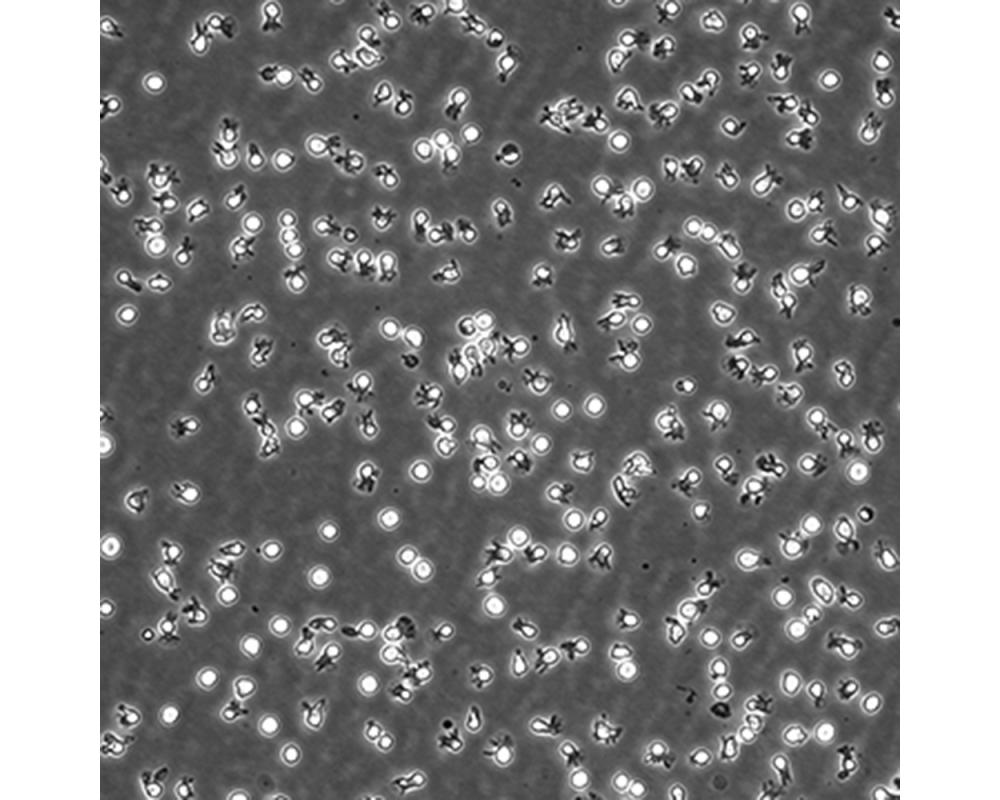

中文名稱 人彌漫大B細胞淋巴瘤細胞

組織來源 彌漫大B細胞淋巴瘤;男性

生長特性 懸浮

傳代方法 Maintain cultures at a cell concentraion between between 1 X 10(5) and 1 X 10(6) viable cells/ml.

培養條件 Atmosphere: Air, 95%; CO2, 5%。Temperature: 37℃